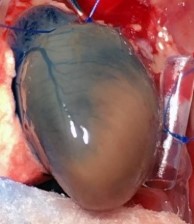

LAD Reperfusion Model: 30 Minute Ischemia with 2 Hour Reperfusion

Pictured: Cardiac Perfusion With Evans Blue Dye To Define Infarct zone.